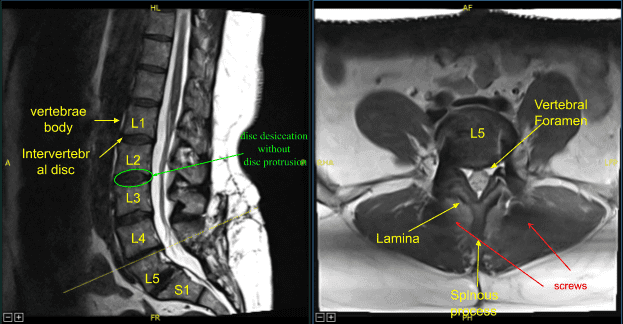

El paciente se presentó en consulta tras dos cirugías lumbares previas realizadas por otro profesional, incluyendo discectomía L5-S1 y TLIF L5-S1. Desarrollaron dolor recurrente en la espalda y los síntomas de las extremidades inferiores, y las imágenes mostraron enfermedad del segmento adyacente con hernia discal L4-L5, estenosis, así como pseudartrosis en L5-S1.

Se transfirieron los datos al ordenador de neuronavegación y se utilizaron técnicas de neuronavegación guiadas por imagen para colocar los tornillos pediculares bilaterales L4, lo cual se logró decorticando un taladro eléctrico de alta velocidad, canulando los pedículos con el localizador de pediculos navegados, sondeando para detectar brechas y midiendo la profundidad con un tap de 5,5 mm y colocando tornillos pediculares de titanio de 6,5×45 mm bajo guía de neuronavegación sin dificultad. Las señales de neuromonitorización estuvieron en tabla durante todo el proceso.

A continuación, realizamos laminectomía L4, facetectomía bilateral con Leksell rongeur, taladro eléctrico de alta velocidad bajo irrigación continua y rongeurs de Kerrison resectando ligamentos flavos de forma fragmentada y expuso el saco cácal, descomprimiéndolo circunferencialmente y neurolizando raíces nerviosas bilaterales L4 con la técnica de Metzenbaum Penfield, y confirmando con ganchos nerviosos. El sangrado epidural se controló mediante electrocauterización bipolar y matriz hemostática de Surgiflo.

El saco tecal se retrajo medialmente hacia el lado derecho con un retractor de raíz nerviosa. La anulotomía se realizó con un bisturí de 15 cuchillas. La discectomía se realizó con afeitadoras de pedal secuenciales y rongeurs de la hipófisis. Las placas finales se preparaban para la artrodesis con raspadores. Recogimos autoinjertos fragmentados, virutas óseas y fragmentamos el proceso espinoso y la lámina resecados.

Se colocó un aloinjerto de matriz ósea desmineralizada en el interespacio y luego se colocó un dispositivo intersomal expansible de titanio bajo guía fluoroscópica tras cubrir estérilmente la unidad C-arm. La AP y la imagen lateral mostraron una posición correcta y luego la jaula se amplió hasta el ajuste adecuado, y la radiografía posterior mostró una buena posición tanto en la línea media como en anteroposterior.

A continuación, se obtuvo un nuevo TAC, que mostró la posición correcta de los nuevos tornillos pediculares y del separador intercarrocés. Los procesos transversales bilaterales de L4, L5 y ala lateral fueron decorizados para la artrodesis. Las varillas precortadas y pre-contorneadas se reflejaban y colocaban sobre los tulipanes desde L4 hasta S1, se aseguraban con tapones de bloqueo y finalmente se apretaban con el dispositivo de par y antitorque.